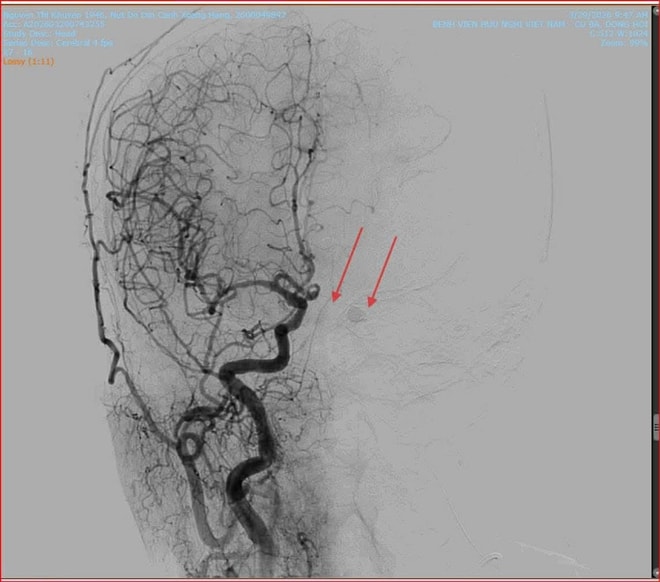

Nhận định đây là ca bệnh có diễn tiến phức tạp, nếu không điều trị kịp thời có thể dẫn đến mù lòa vĩnh viễn hoặc xuất huyết não, ê-kíp các bác sĩ can thiệp mạch của hai bệnh viện đã quyết định thực hiện phương pháp can thiệp nội mạch nút lỗ rò. Dưới sự hỗ trợ của hệ thống chụp mạch số hóa xóa nền (DSA), các bác sĩ đã khéo léo đưa ống thông (microcatheter) từ động mạch đùi lên vị trí tổn thương tại xoang hang.

Tại đây, vật liệu can thiệp Coil và keo sinh học được đưa vào để bít kín lỗ rò một cách chính xác nhất, giúp tái lập lại dòng chảy bình thường cho mạch máu não. Ca can thiệp diễn ra thành công tốt đẹp.

Vị trí rò động mạch (ảnh trái) và sau khi can thiệp bít lỗ rò (ảnh phải).